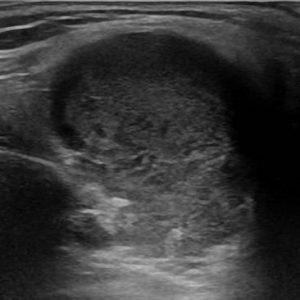

Bệnh Sjögren

Lượt xem: 201» 16-01-2021 -

Bệnh Sjögren

Lượt xem: 152» 16-01-2021 -

Bệnh Sjögren

Lượt xem: 162» 16-01-2021 -

Bệnh Sjögren

Lượt xem: 163» 16-01-2021 -